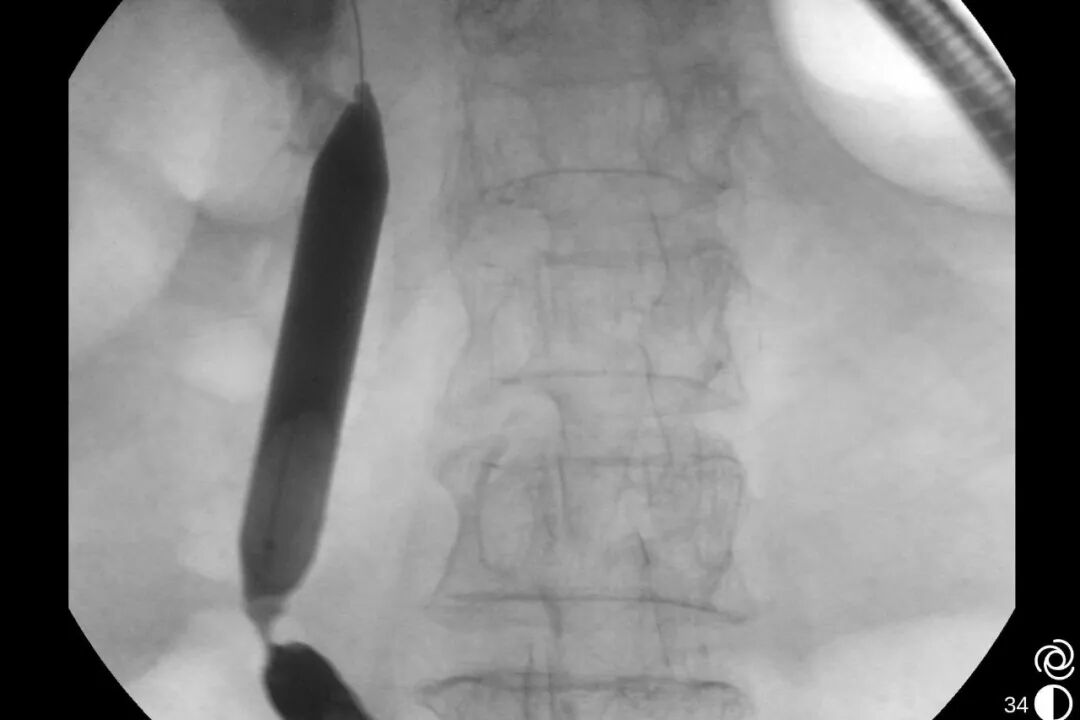

图片

术中-十二指肠乳头

术中胃镜戴透明粘膜吸套进镜,可见胃、十二指肠、空肠呈B-II式术后改变,吻合口发红。经团队仔细查找,于输入袢找到十二指肠大乳头,插入三腔括约肌切开刀,并顺利将导丝送入胆总管。造影验证,可见胆总管明显扩张,直径最宽处约16mm,中段见一长条形结石影,约13x12mm。切开乳头后,扩张乳头括约肌及胆总管括约肌,用特制取石导管及取石网篮取出大量黄色块状结石及碎渣样结石。术后置入鼻胆引流管引流,顺利结束手术